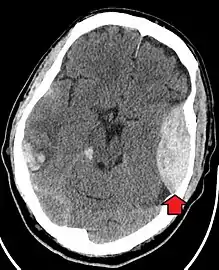

Blunt cranial trauma

The primary clinical concern with blunt trauma to the head is damage to the brain, although other structures, including the skull, face, orbits, and neck are also at risk.[8] Following assessment of the patient's airway, circulation, and breathing, a cervical collar may be placed if there is suspicion of trauma to the neck. Evaluation of blunt trauma to the head continues with the secondary survey for evidence of cranial trauma, including bruises, contusions, lacerations, and abrasions. In addition to noting external injury, a comprehensive neurologic exam is typically performed to assess for damage to the brain. Depending on the mechanism of injury and examination, a CT scan of the skull and brain may be ordered. This is typically done to assess for blood within the skull, or fracture of the skull bones.[17]

Traumatic brain injury (TBI)

Traumatic brain injury (TBI) is a significant cause of morbidity and mortality and is most commonly caused by falls, motor vehicle crashes, sports- and work-related injuries, and assaults. It is the most common cause of death in patients under the age of 25. TBI is graded from mild to severe, with greater severity correlating with increased morbidity and mortality.[17][18]

Most patients with more severe traumatic brain injury have of a combination of intracranial injuries, which can include diffuse axonal injury, cerebral contusions, and intracranial bleeding, including subarachnoid hemorrhage, subdural hematoma, epidural hematoma, and intraparenchymal hemorrhage.[8][17] The recovery of brain function following a traumatic injury is highly variable and depends upon the specific intracranial injuries that occur, however there is significant correlation between the severity of the initial insult as well as the level of neurologic function during the initial assessment and the level of lasting neurologic deficits.[17] Initial treatment may be targeted at reducing the intracranial pressure if there is concern for swelling or bleeding within this skull, which may require surgery such as a hemicraniectomy, in which part of the skull is removed.[8][17]